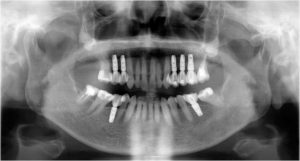

長い間お疲れさまでした。この方は、前歯に審美的なインプラントを入れるため、抜歯後4ヶ月待ち、仮歯で歯肉が成熟するのを数が月待っていたりした為に、完成まで時間がかかってしまいました。

虫歯治療などは短期間で終えることができるのですが、歯ぐきをいじり出すとどうしても治癒期間が必要となり長くなってしまいます。それもこれも奇麗な仕上がりのために欠くことのできないものです。何卒ご容赦を!

- 術前

- 術後

- インプラント手術直後のレントゲン